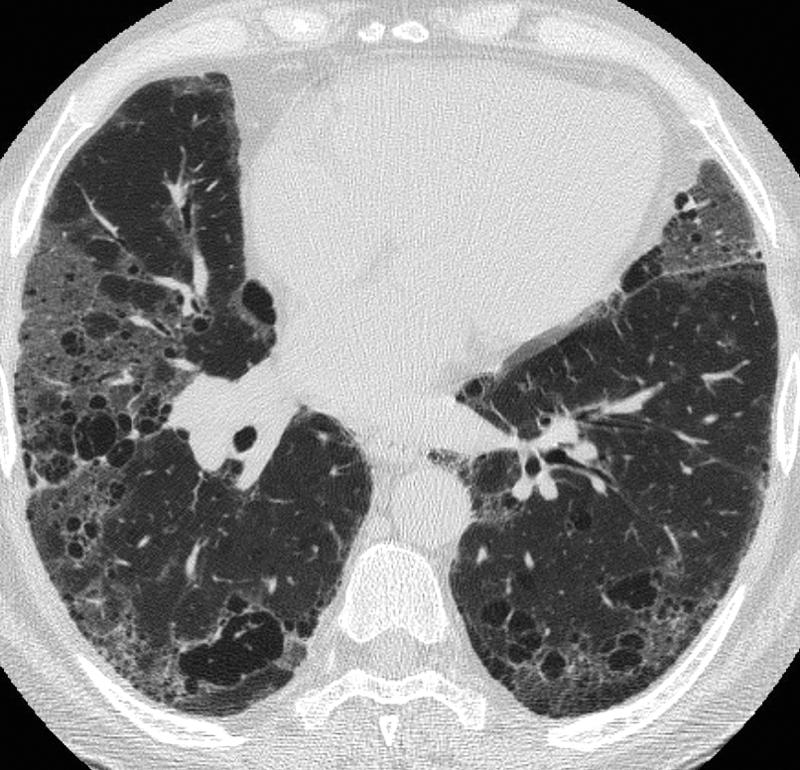

Pulmonary Fibrosis

IPF

Case 8d